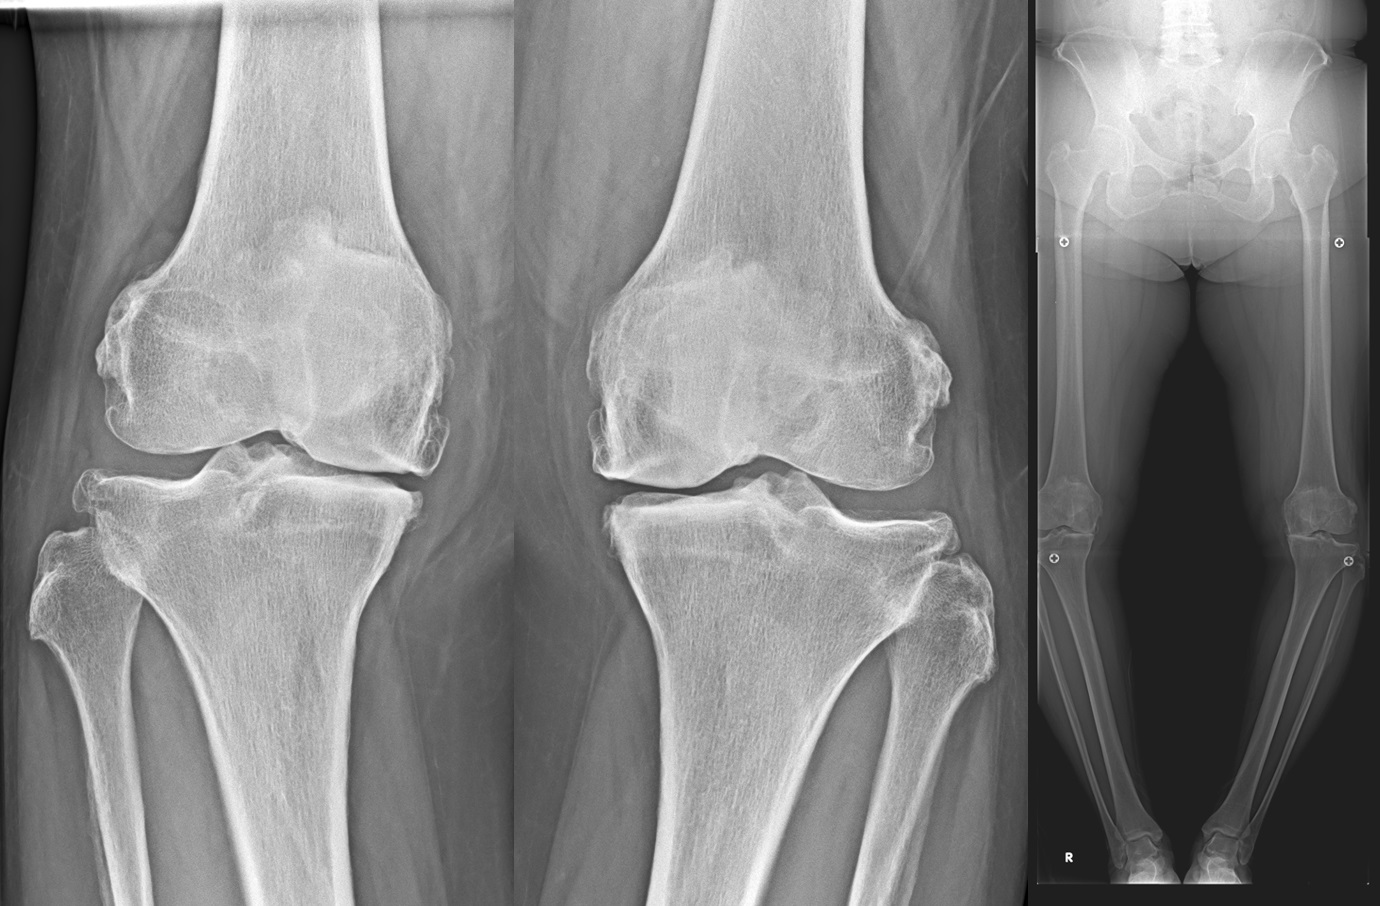

変形性膝関節症(knee osteoarthritis: 膝OA)

変形性膝関節症は、加齢などにより関節軟骨や半月板が変性・消失する疾患で膝関節痛や可動域制限を生じ、病態が進行すると日常生活動作(ADL)や生活の質(QOL)が低下します。わが国では40歳以上の有病者数は2500万人と推定されており、今後の高齢者人口の増加に伴い有病者数も増加すると考えられています。

高位脛骨骨切り術(high tibial osteotomy: HTO)

初期の変形性膝関節症や大腿骨顆骨壊死などに適応があります。

O脚変形のために内側に偏った荷重線を、自分の骨を骨折させ角度を変えることにより、比較的きれいな軟骨の存在する外側に荷重線を移動させる手術です。荷重線が移動することによって膝の痛みが緩和されます。

人工膝関節単顆置換術(unicompartmental knee arthroplasty: UKA)

膝関節の内側または外側のみの変形に対して適応があります。

人工膝関節全置換術(total knee arthroplasty: TKA)

末期の変形性膝関節症に対してはTKAを行います。